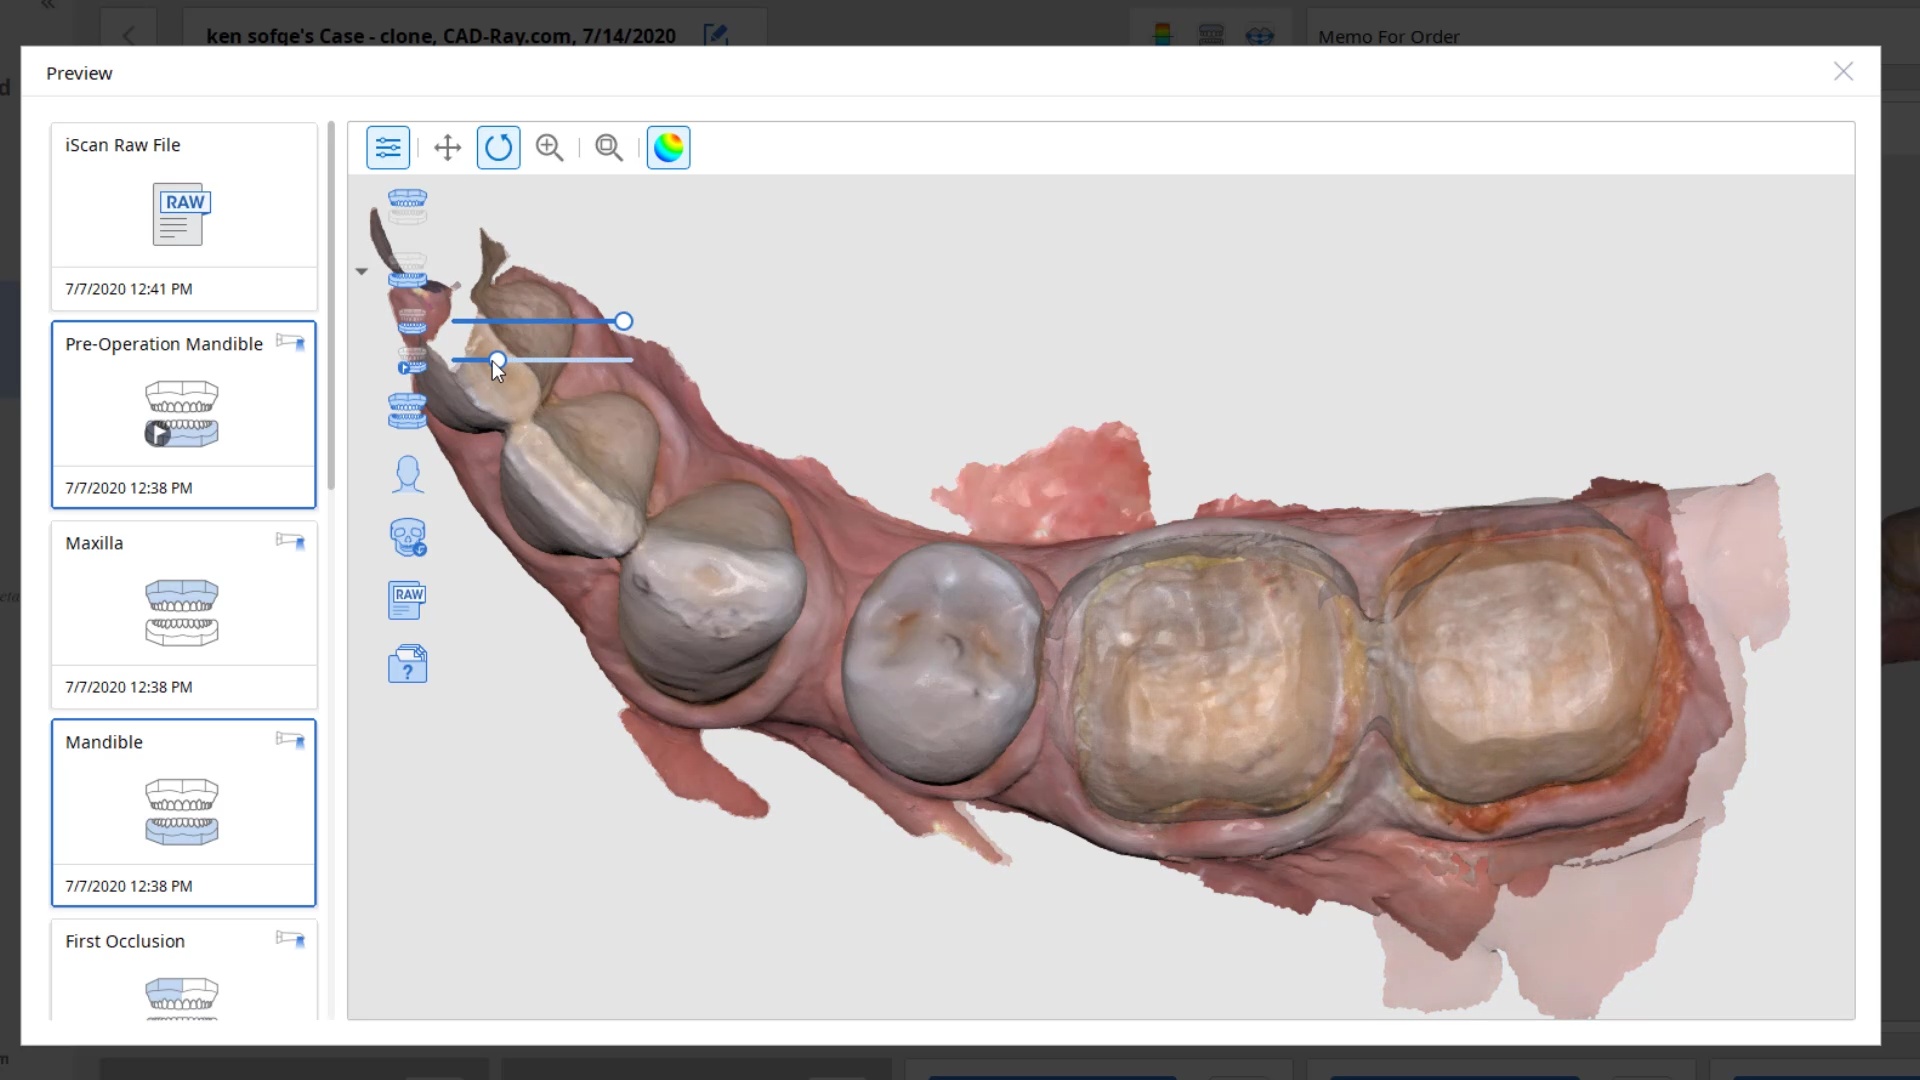

For our advanced users who mill in house or what to speed up their digital impressions we advocate taking advantage of digital dentistry’s unique features that allow you to take impressions over a period of time and segments, building larger models over different sequences and time. In this particular case we have two molars in the lower left quadrant that warranted replacement. The traditional method would be to prep both, isolate both, retract both, and take your final impression, but we will approach this as if there are two separate patients involved

For the second molar, we will take advantage of the anesthesia time and capture the first bite, the opposing, the pre-existing situation and then crop out the preparation area digitally. Once the tooth is prepared, we will check for proper reduction. We will then take the second bite to verify the vertical dimension has not changed.

While the second molar is being designed and milled in the first case, we will launch a second window by cloning the first case. All the data remains the same and this time we crop out the first molar digitally and protect the rest of the arch. Once the first molar is isolated, it is digitally captured and then designed and milled.

To manage the contact between the two crowns, there are many advanced applications. Here is a simple explanation of how we use the prep model from case 1 as the pre-op model for case two. Since the second molar in case 1 made contact with the distal wall of the first molar, when we design the crown for the first molar in case 2, all we have to do is make sure the distal wall is flush to the pre-op. This guarantees us a contact between the two. There are lots of shortcuts to this puzzle once you get the basics of digital impressions under your belt.